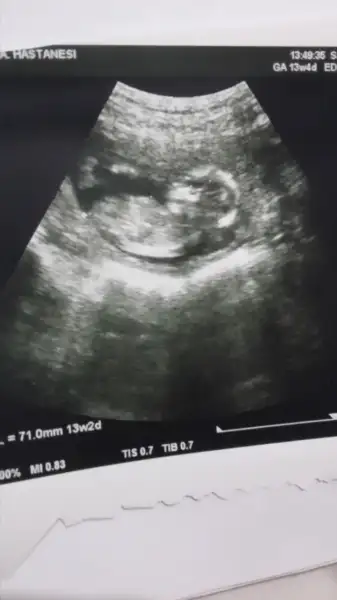

Kizlar biz su an 13+4 haftaligiz ama bu gune kadar doktorum cinsiyeti hakkinda bi yorum yapmadi. Acaba fotosunu atarsam benim icin bakabilir misiniz? Şimdiden tesekkur ederim hepinize.Eki Görüntüle 2086677